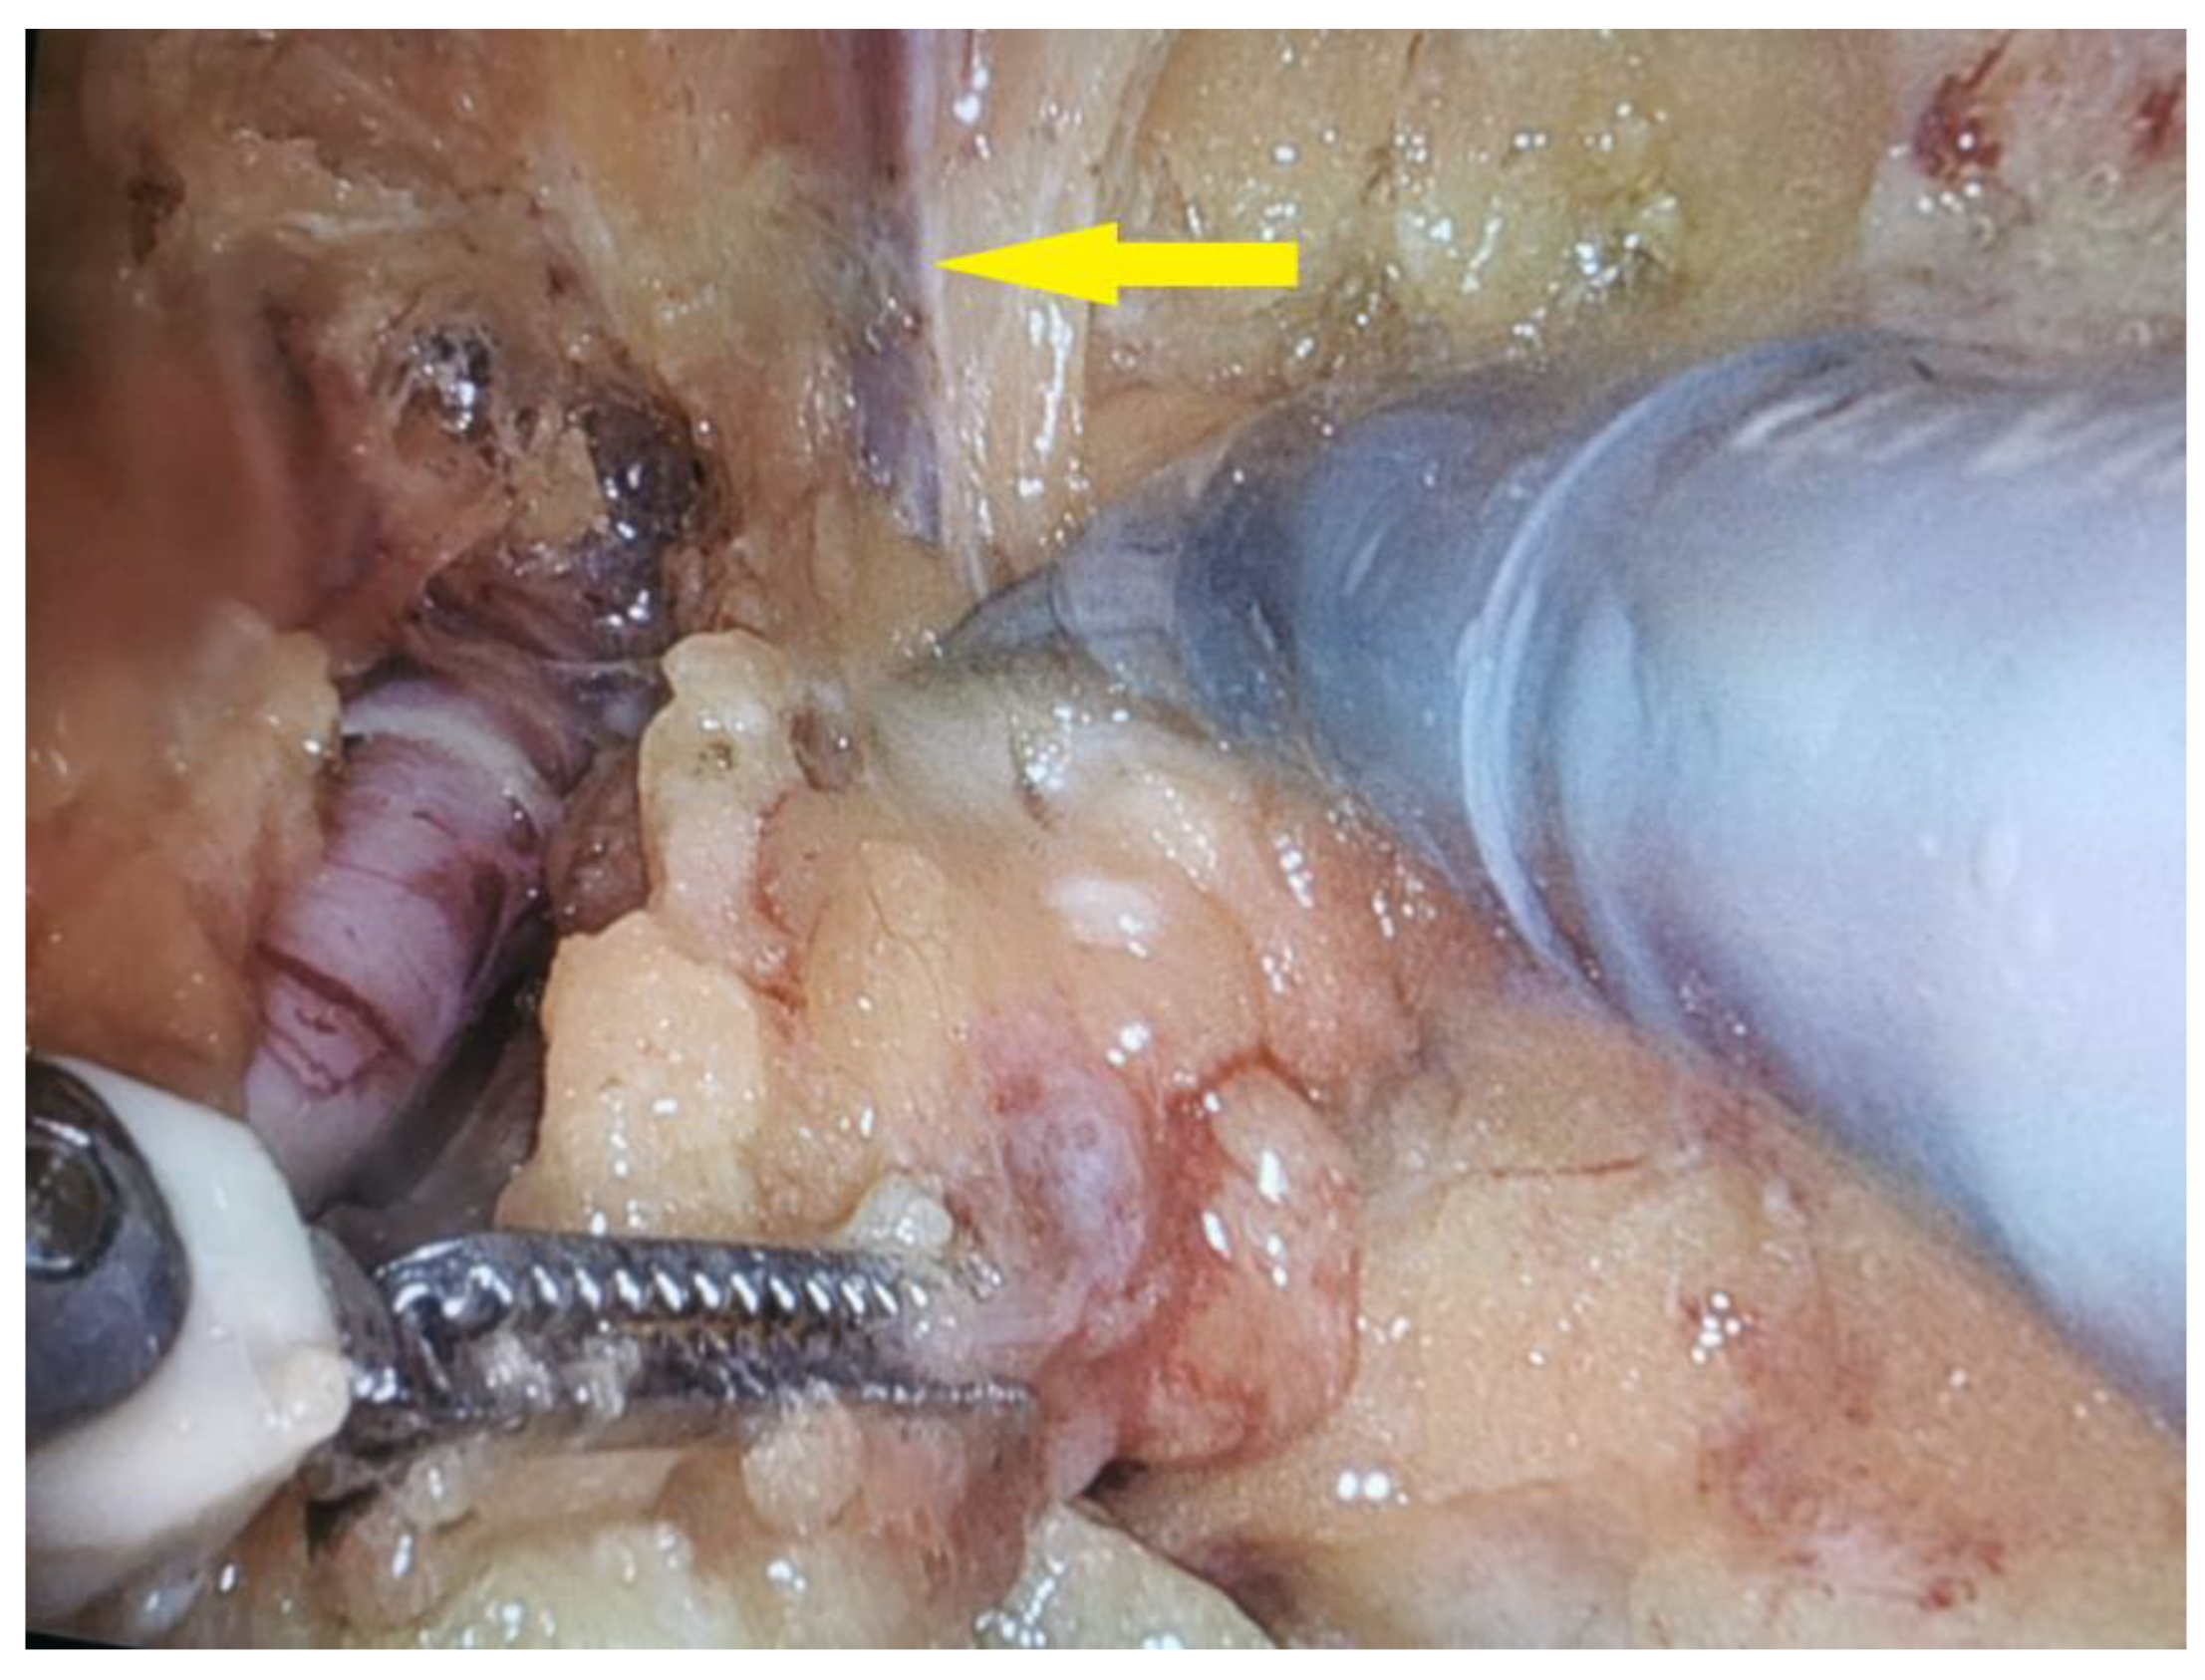

2.4. Salvage Surgical Intervention